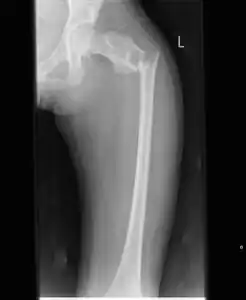

X-ray: Simple bone cyst in left upper arm of 13 year old

A simple bone cyst, also known as a solitary bone cyst, is a non-cancerous cavity in bone, filled with a yellow-colored fluid, usually in a long bone of a child.[1][2] It is usually discovered by chance as often there are no symptoms, but may present with an unexpected broken bone, pain, swelling or reduced movement.[1][2]

Most simple bone cysts do not cause any symptoms and are discovered as accidental findings on radiographs or CT scans made for other reasons.[3] Although it can form in any bone structure, it is predominantly found in the long bone of the upper arm near the shoulder, and long bone of the thigh near the hip.[6] Large lesions can cause nearby areas of bone to thin, which may result in a fracture and cause pain.[1][2] There may be a swelling or problem in moving the affected bone.[1]

Simple bone cysts are often found incidentally on X-rays. About 90 to 95% of the lesion is found in metaphysics of long bones. The cyst is centered, oblong in shape along the long axis of a long bone. Rarely, they are large and multicameral and are found in diaphysis. When fracture is present, there may be a small bone fragment migrated in the cystic fluid. This is called "fallen fragment sign" which is diagnostic of simple bone cyst. Besides, a bubble migrating upwards (known as "rising bubble sign") is another feature suggesting of simple bone cyst.[7]

Most simple bone cysts are diagnosed in growing bone in under 20 year olds.[1] Around half occur in the long bone of the upper arm and a quarter in the long bone of the thigh.[1] Males are twice as likely to be affected than females.[1]